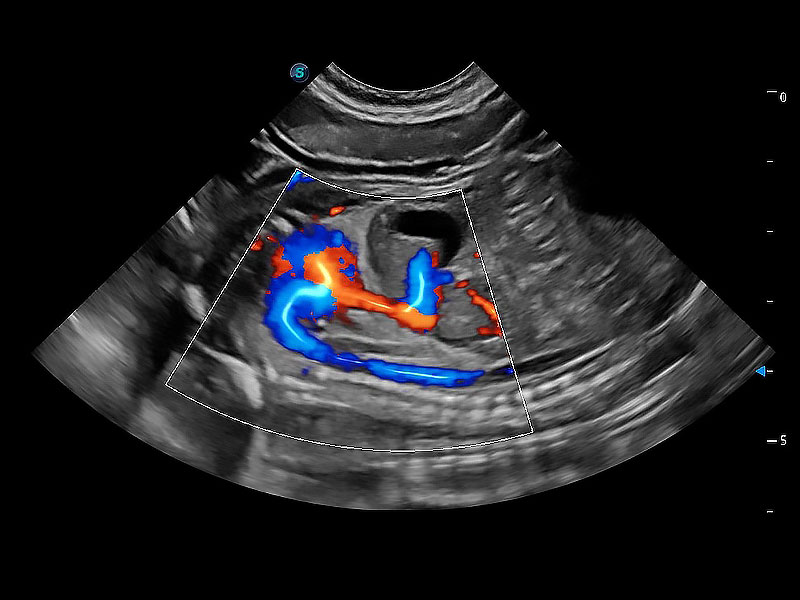

极大提升超低速微细血流的检出能力,同时更精准地滤除软组织和超声信号,为兽用医生提供以往无法通过常规血流获得的疾病诊断信息。

在传统二维血流成像的基础上,呈现血流的立体感,具有动感的生命力之美。即便是微小的血管也能轻松应对,提高了血流的视觉敏感性。

ProPet 80 配备了丰富的心脏探头群、先进的成像技术和专业的心脏测量工具,可帮助动物医生为不同体型和生理结构的动物提供心脏和心肌功能的全面评估。